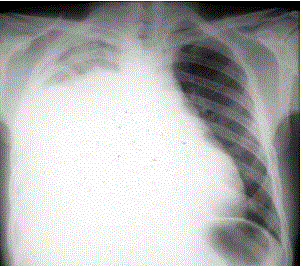

患者男,34岁。进行性胸闷、气促1个月余,伴有干咳、右胸隐痛以及消瘦,无咯血、发热、盗汗、潮热等。(提示 胸部X线检查如图所示)根据胸腔穿刺结...

问题 患者男,34岁。进行性胸闷、气促1个月余,伴有干咳、右胸隐痛以及消瘦,无咯血、发热、盗汗、潮热等。 (提示 胸部X线检查如图所示) 根据胸腔穿刺结果,患者胸腔积液的性质和病因最可能是(提示 患者诊断性胸腔穿刺结果:胸腔积液呈淡红色,细胞数600×10/L,单核细胞65%,蛋白32 g/L,葡萄糖1.8 mmol/L,LDH 550 U/L,ADA 18 U/L,CEA 125 μg/L。)

选项 A.漏出性胸腔积液 B.渗出性胸腔积液 C.低蛋白血症所致胸腔积液 D.结核性胸腔积液 E.恶性胸腔积液 F.类肺炎性胸腔积液

答案 BE

解析 BE